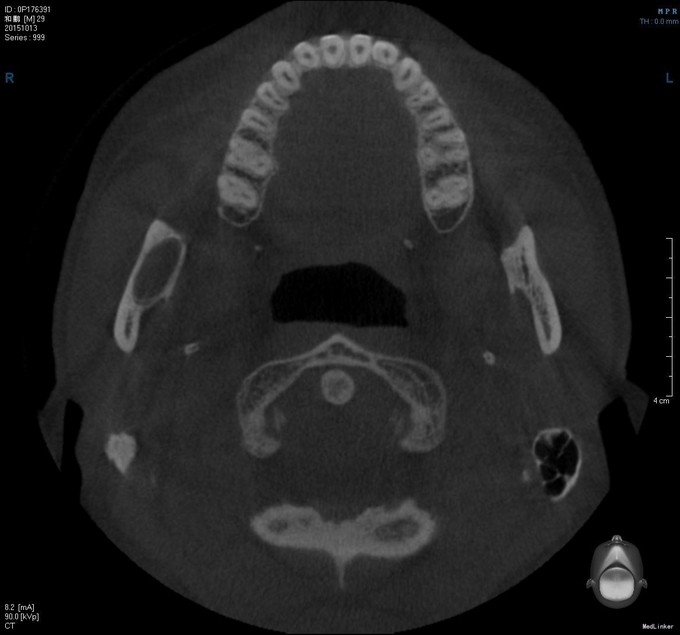

双侧颜面部基本对称,右下颌未见明显隆起,表明皮肤无异常,皮温无升高,无压痛,无右下唇麻木,无张口受限,开口度4.0cm,开口型"↓",双侧髁突动度一致,开闭口未闻及关节明显弹响音。口内检查:右下8未萌,牙齿无松动,无叩痛,右下颌未见明显隆起,无瘘道,双侧头颈部无扪及明显肿大淋巴结。我院CT检查:右下8埋伏于骨内,牙冠偏远中,牙根偏近中,根尖突向下颌神经管。右下8区至右下颌升支近乙状切迹下方见类椭圆形骨质密度减低影,边界清楚,大小约4.4*1.5*.8cm,边缘见骨质增生。其内包含右下8牙冠。肿物膨胀尚不明显,右下8区牙槽嵴顶骨质吸收消失。病变下方紧邻下颌神经管,局部管壁吸收。提示:右下颌骨囊肿:牙源性角化囊性瘤?

初 步 诊 断: 1.右下颌骨肿物待查:牙源性角化囊性瘤? 出 院 诊 断: 1.牙源性角化囊性瘤 2.48埋伏阻生牙 在手术室全麻下行右下颌升支肿物刮除+48复杂牙拔除术+右下颌骨区骨皮质术+邻近瓣转移修复术。术后予预防感染、消肿等对症治疗。